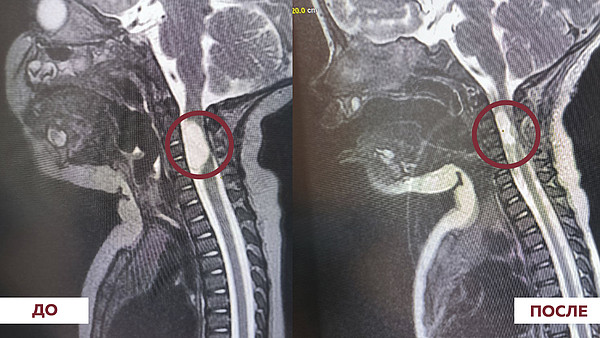

операция киста.